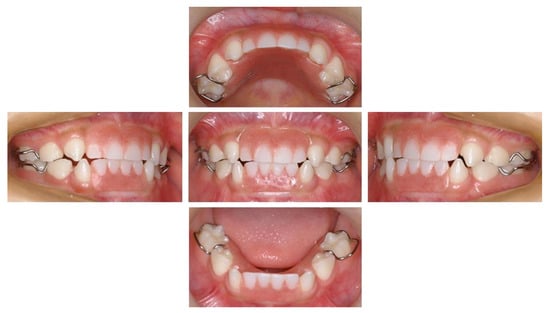

2. Case Presentation